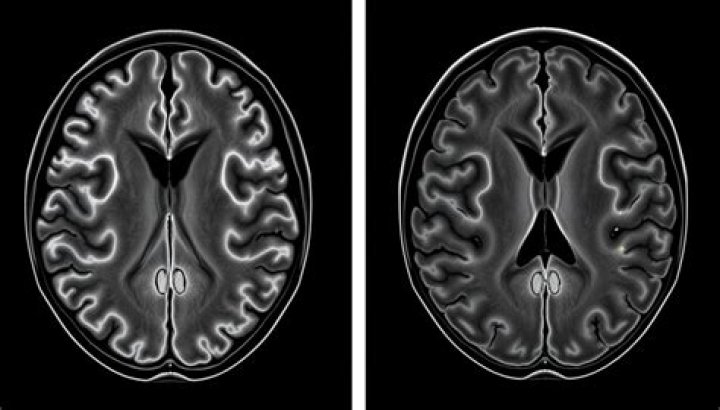

What does white matter changes on brain MRI mean?

White matter disease is commonly detected on brain MRI of aging individuals as white matter hyperintensities (WMH), or 'leukoaraiosis.” Over the years it has become increasingly clear that the presence and extent of WMH is a radiographic marker of small cerebral vessel disease and an important predictor of the life- ...

How common are white matter lesions?

White-matter lesions

They are highly frequent in the elderly population. In people aged 60–70 years the prevalence is about 87%, whereas the prevalence at the age of 80–90 years even approaches 100% (de Leeuw et al., 2001; Launer, 2004).

Is white matter on brain serious?

Originally, white matter disease was considered a normal, age-related change. But over the last decade, medical experts have come to understand that the presence of large areas of disease in the white matter of the brain are associated with cognitive decline and dementia in patients.

Can stress cause white matter lesions?